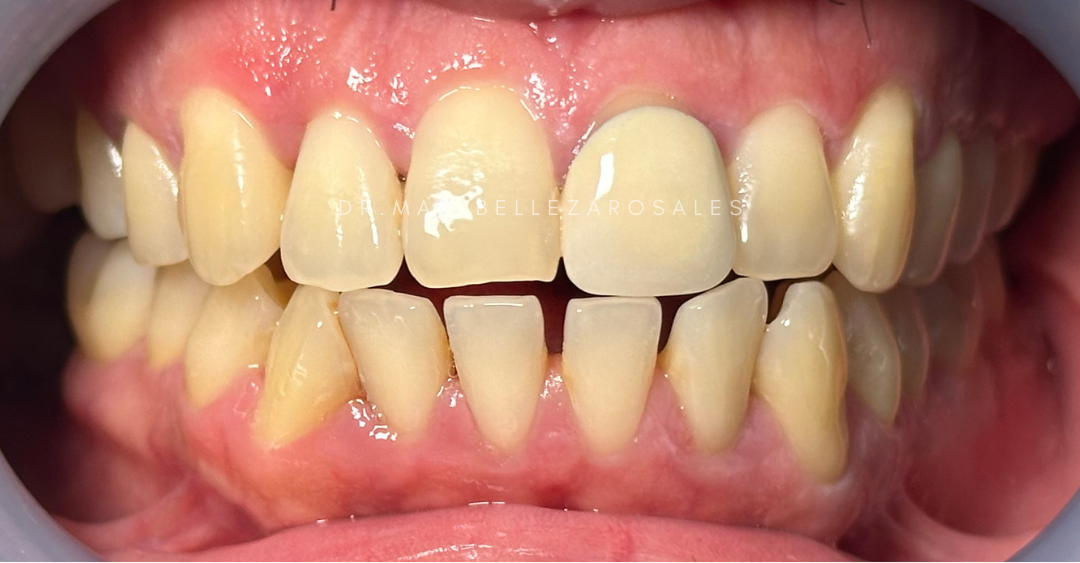

A zirconia bridge is a fixed dental solution used to replace one or more missing teeth by filling the gap with strong, natural-looking artificial teeth supported by nearby teeth. It is durable, gentle on the gums, and designed to blend seamlessly with your smile while allowing you to eat, speak, and smile comfortably

A zirconia crown is a tooth-colored dental cap used to restore a damaged, weakened, or heavily filled tooth. It provides exceptional strength, protects the remaining tooth structure, and offers a natural appearance while allowing you to chew and smile with confidence.